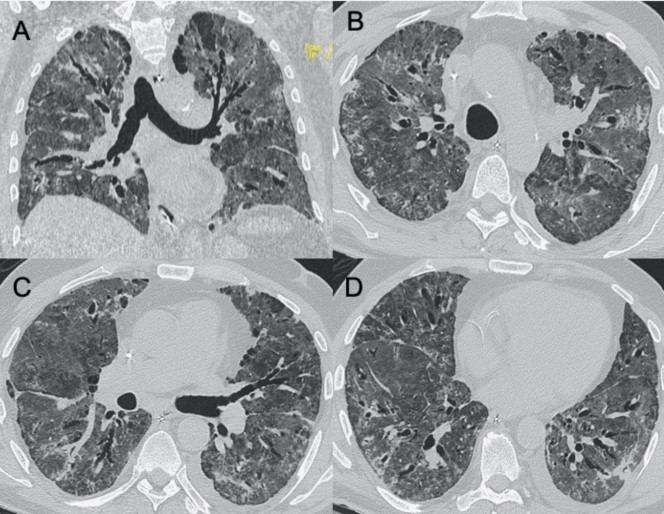

?HINI流感病毒

● CXR:?jiǎn)蝹?cè)/雙側(cè)GGO,伴或不伴實(shí)變區(qū)域,主要分布于支氣管血管周圍和胸膜下。

● CT:?jiǎn)蝹?cè)/雙側(cè)GGO,伴或不伴實(shí)變區(qū)域,主要分布于支氣管血管周圍和胸膜下。

圖4 圖(A-D)為一例H1N1相關(guān)肺炎并發(fā)急性呼吸窘迫綜合征(respiratory distress syndrome,ARDS)的影像,可見(jiàn)彌漫性和雙側(cè)GGO以及牽引性支氣管擴(kuò)張。